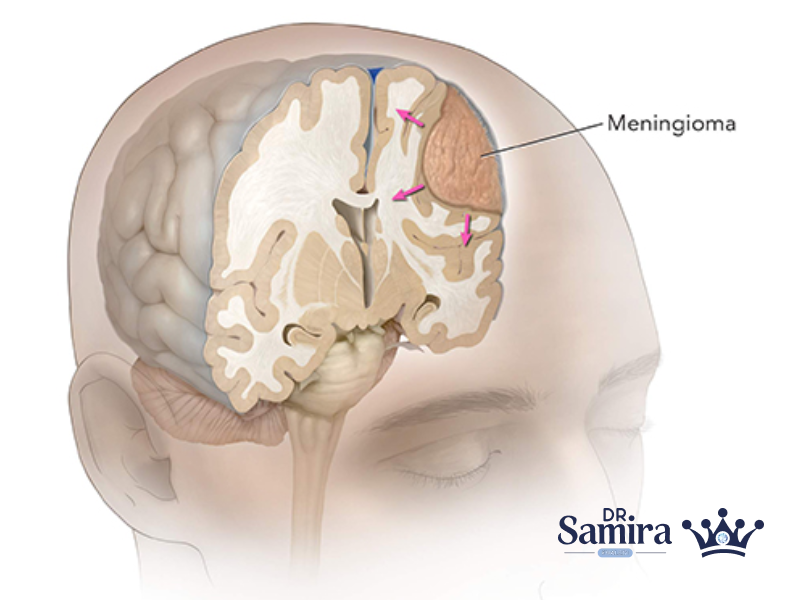

مننژیوم گرید یک یکی از شایع ترین تومورهای مغزی با منشا سلول های مننژ است که...

مننژیوم گرید ۳ یکی از تهاجمی ترین انواع تومورهای مغزی است که تحت عنوان مننژیوم آناپلاستیک...

مننژیوم آتیپیک یا گرید دو (Atypical Meningioma) یکی از انواع تومورهای سیستم عصبی مرکزی است که...